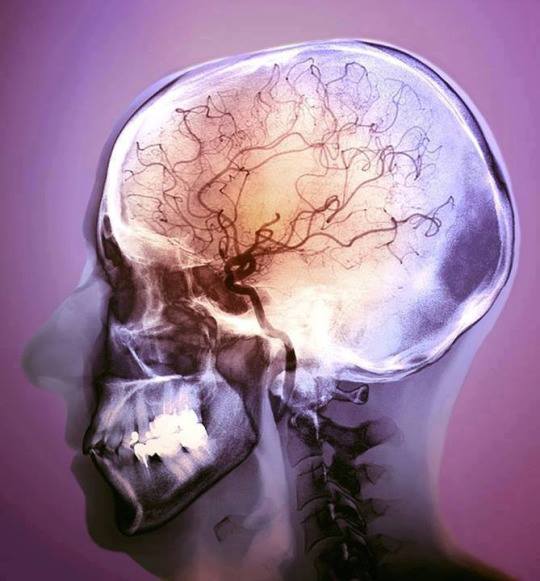

Barwny angiogram mózgu 48-letniego pacjenta po udarze

Angiografia lub arteriografia jest techniką obrazowania medycznego wykorzystywaną do wizualizacji wnętrza naczyń krwionośnych oraz organów ciała, zwracającą szczególną uwagę na tętnice, żyły oraz komory serca.